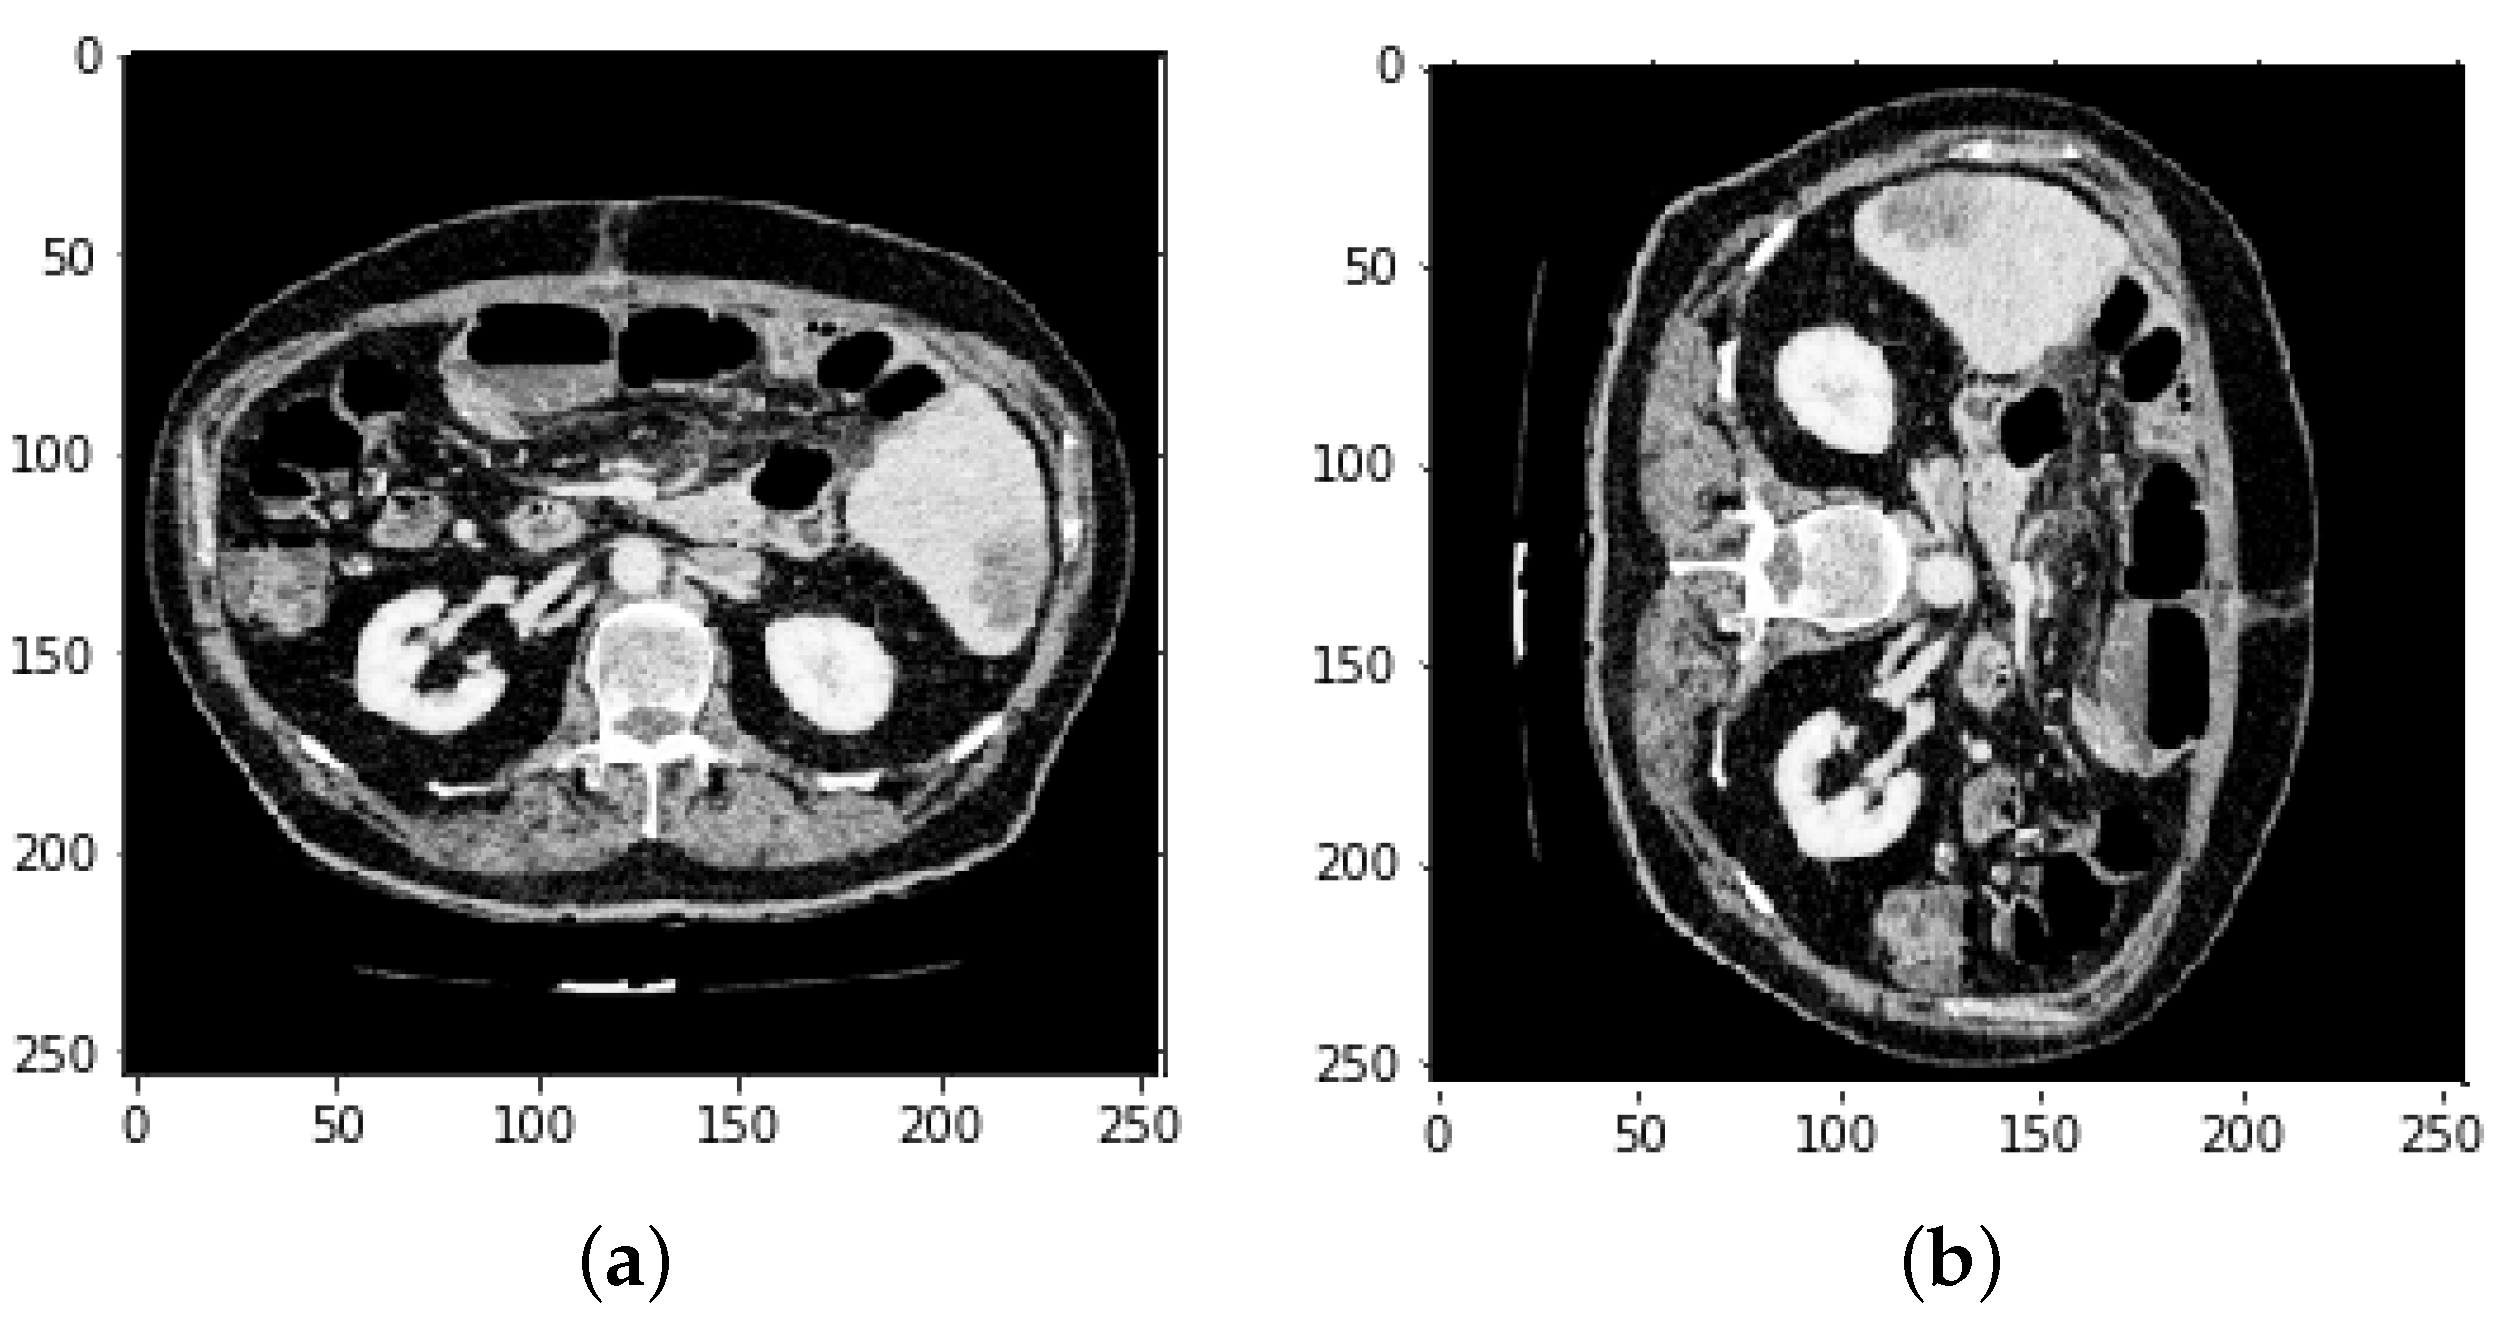

4.1. Segmentation Process of Liver and Liver Tumor

3.4. Defining Region of Interest (ROI)